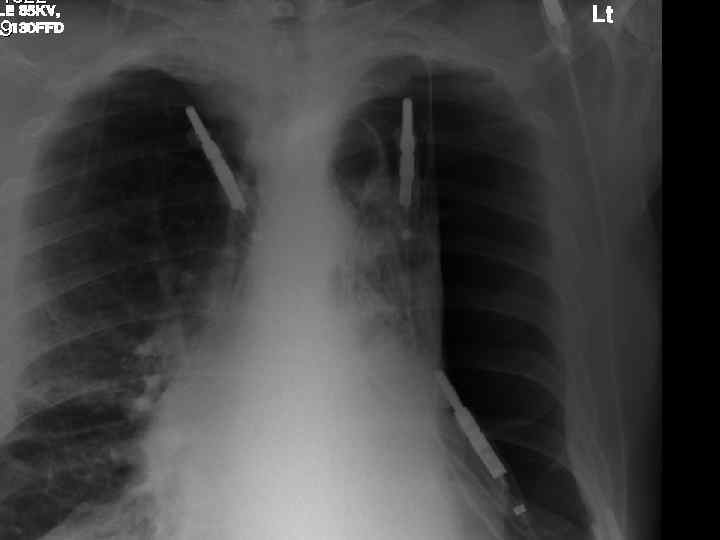

Examination n n n Anxious, gasping for breath, holding arms on trolley, Abdominal muscles used for breathing Central cyanosis Pulse 106 bmp regular HS I + II + 0 Apex beat laterally displaced Pitting right ankle oedema No sacral oedema

Respiratory R n n n L Resp rate 22 pm Trachea central Uneven lung expansion Hyperinflated upper chest Hyperresonant percussion Exp wheezing Insp crackles

Impressions n Pneumothorax n COPD/Fibrosing alveolitis n AHA n Congestive heart failure n Newly diagnosed Diabetes mellitus

Investigations. n CXR n CT n Arterial blood gases

Intercostal drainage n Chest drain into triangle marked by: Apex of axilla n Nipple (4 th ics, mid clav. line) n Base of scapula n n Complications: Penetration of major organs n Pleural infection n Surgical emphysema n